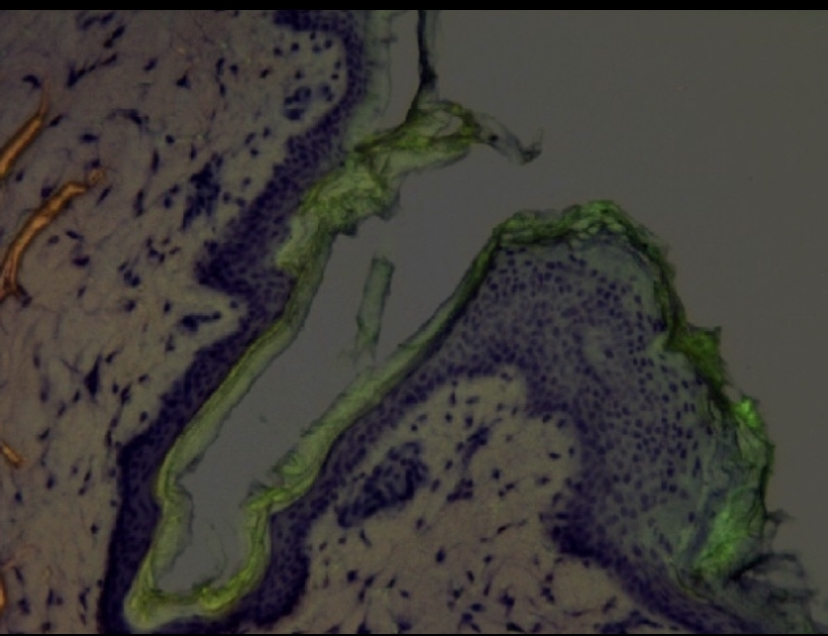

Cyclodextrins are molecules that binds to other chemicals to make a complex that is more soluble in water. It makes sense these makes the particle size bigger in the process. Cyclodextrins struggle to travel through intact skin. However cyclodextrins can penetrate down to the follicle.

The proposed theory is to use these with dutasteride, finasteride or RU58841, and make them selectively penetrate down to the follicle but not go systemic.

This article propose using cyclodextrins to do just this: